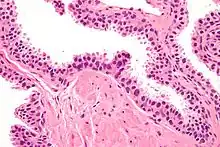

| Micrograph showing high-grade prostatic intraepithelial neoplasia. H&E stain. | |

HGPIN typically has one of four different histologic patterns:[2]

- tufted (fascicular patterning)

- micropapillary,

- cribriform and,

- flat.

Its cytologic features are that of prostatic adenocarcinoma:

- presence of nucleoli,

- increased nuclear-to-cytoplasmic ratio and,

- increased nuclear size.

Microscopically, PIN is a collection of irregular, atypical epithelial cells. The architecture of the glands and ducts remains normal. The epithelial cells proliferate and crowding results in a pseudo-multilayer appearance. They remain fully contained within a prostate acinus (the berry-shaped termination of a gland, where the secretion is produced) or duct. The latter can be demonstrated with special staining techniques (immunohistochemistry for cytokeratins) to identify the basal cells forming the supporting layer of the acinus. In prostate cancer, the abnormal cells spread beyond the boundaries of the acinus and form clusters without basal cells. In HGPIN, the basal cell layer is disrupted but present. PIN is primarily found in the peripheral zone of the prostate (75-80%), rarely in the transition zone (10-15%) and very rarely in the central zone (5%), a distribution that parallels the zonal distribution for prostate carcinoma.[7]

Several architectural variants of PIN have been described, and many cases have multiple patterns. The main ones are tufting, micropapillary, cribriform, and flat. Although these different appearances may cause confusion with other conditions, they have not been found to be of clinical importance. Rarer types are signet-ring-cell, small-cell-neuroendocrine, mucinous, foamy, inverted, and with squamous differentiation.[3]